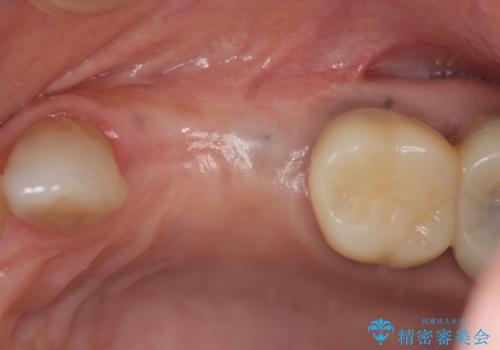

今回はが原因で失われてしまった骨の幅を回復することで長期的な予後を見込めるインプラント治療を行うことができました。